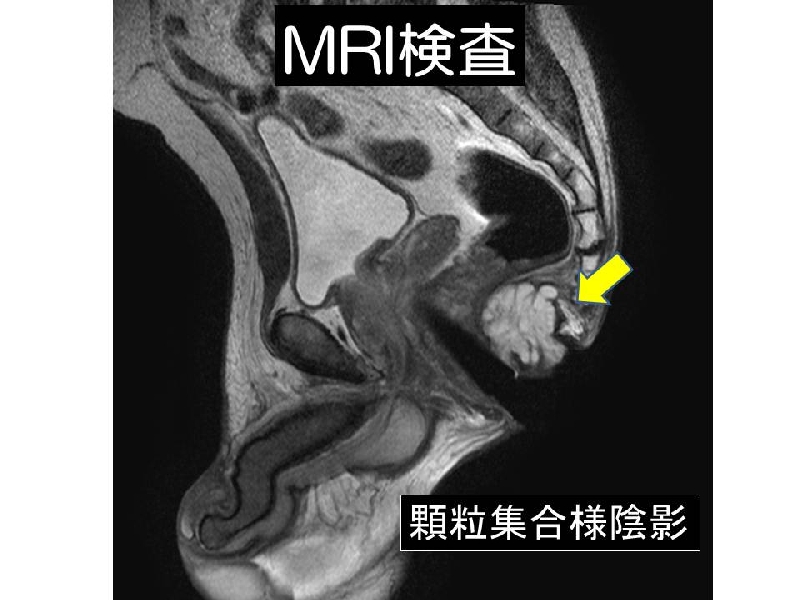

Mucinous adenocarcinoma associated with chronic fistula in ano is rare, and diagnosis is often difficult. Four cases of mucinous adenocarcinoma arising from longstanding anal fistulas are presented. Endoanal ultrasonography (SSD-Prosound 4000, ALOKA, Tokyo) revealed characterisric features; those consist of a hypoechoic bulging lesion containing heterogenous hyperechoic spots with “ honey comb appearance”. This is due to the fact that mucinous adenocarcinomas usually contain many small mucous lakes. This finding shows the implications in diagnosing mucinous adenocarcinoma arising from fistula in ano.